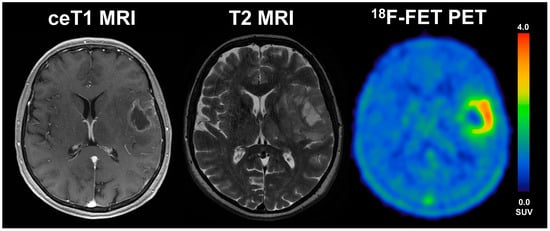

Figure 4.

57-year old female with glioblastoma (WHO grade IV, IDH wildtype, MGMT unmethylated) and an overall survival of 4.9 months (STS). The diameter of CE on T1 MRI was 31 mm, the volume of CE was 6 mL, the BTV in FET-PET was 39.1 mL, the TTPmin was 12.5 min and TBRmax was 3.9. The patient underwent radiochemotherapy.